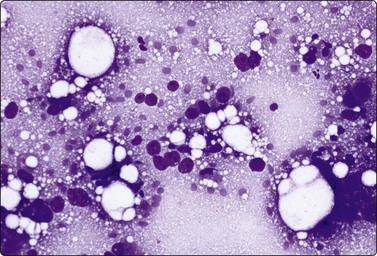

Myeloid metaplasia (Fig. 10.34)

The findings in myeloid metaplasia include normoblasts, myelocytes and megakaryocytes intermingled with the cells of normal splenic tissue. Normoblasts are easily recognized by their relatively small, round, hyperchromatic nuclei and their homogeneous, dense eosinophilic or amphophilic cytoplasm. Megakaryocytes may be mistaken for malignant neoplastic cells but should be recognizable by the giant, lobulated nucleus and the abundant, granular cytoplasm. Myelocytes have specific cytoplasmic granules. All these features are best seen in MGG-stained smears.234

image

Fig. 10.34 Myeloid metaplasia

(A) Megakaryocyte and several erythroblasts adjacent to smeared lymphoid cells (MGG, HP); (B) Erythroblasts, myelocytes, lymphoid cells (MGG, HP).